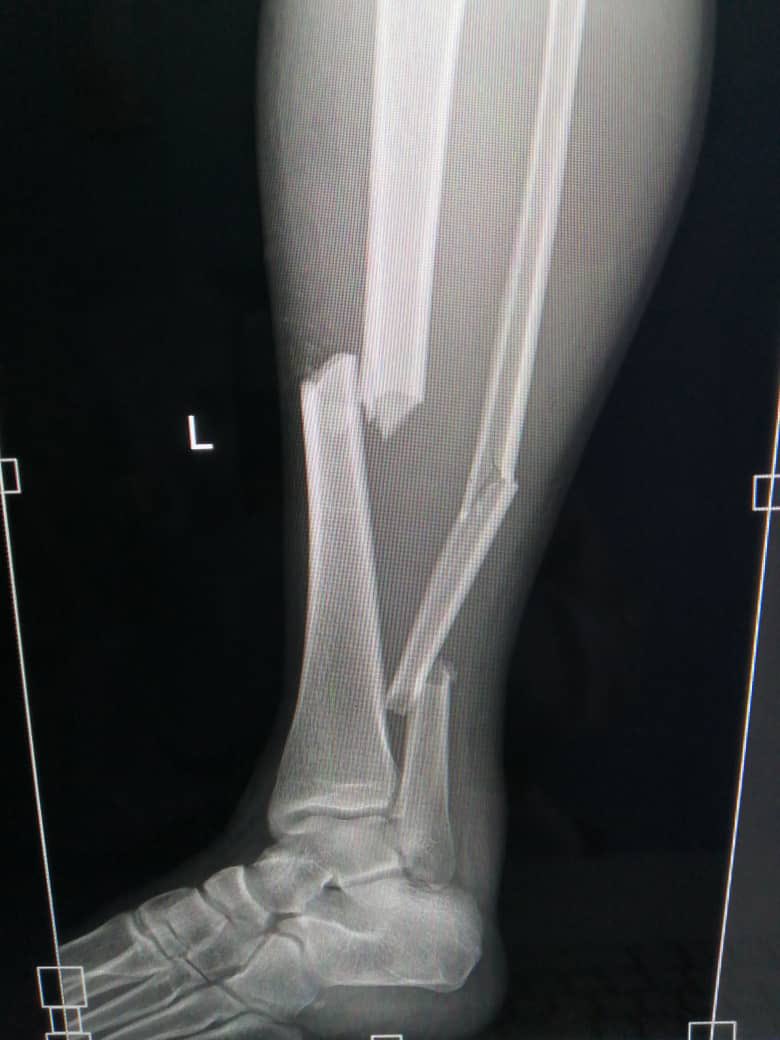

APPEALING FOR HELP FOR TINOTENDA MUNAVA Tinotenda Munava (22years) had an accident on 14 August 2025 and was taken to Harare Central Hospital. His leg was broken in 3 places. See picture below. The doctors now recommend a surgical procedure to hold the broken bones together

APPEALING FOR HELP FOR TINOTENDA MUNAVA

Tinotenda Munava (22years) had an accident on 14 August 2025 and was taken to Harare Central Hospital. His leg was broken in 3 places. See picture below.

The doctors now recommend a surgical procedure to hold the broken bones together